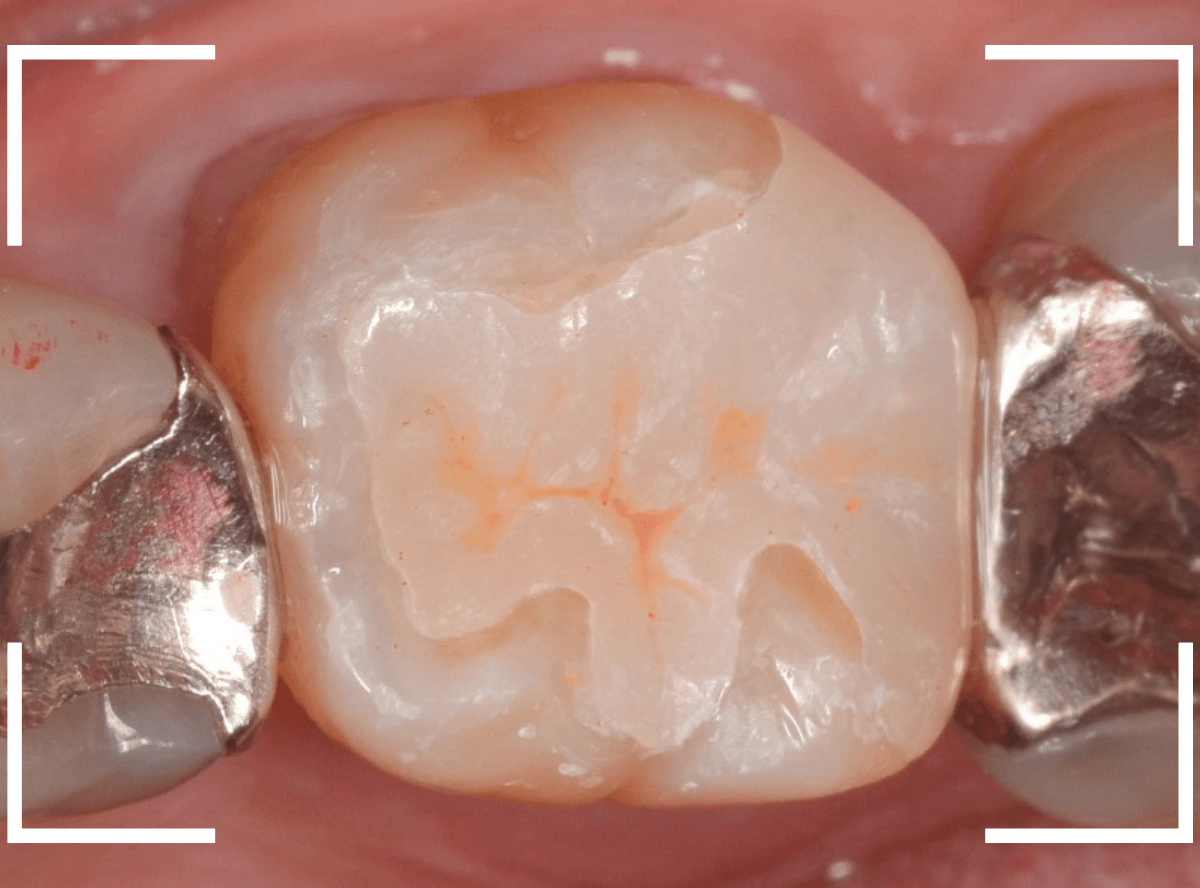

治療後の状態です。

ジルコニア・インレーはE-MAX・インレーより審美性に劣るのですが、患者さんにもご満足いただける仕上がりになり、ホッとしました。